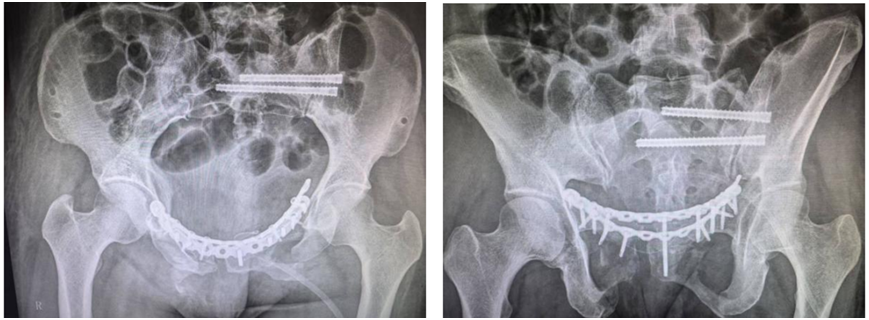

创伤中心副主任医师李宏彦及其团队完成了该手术,整台手术的出血量只有200毫升。患者苏醒后,双下肢感觉活动无异常。

术后拍片显示骨盆复位及内固定位置良好。